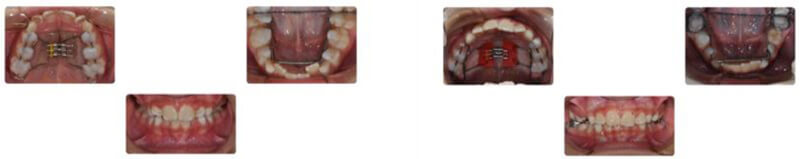

Case Report: